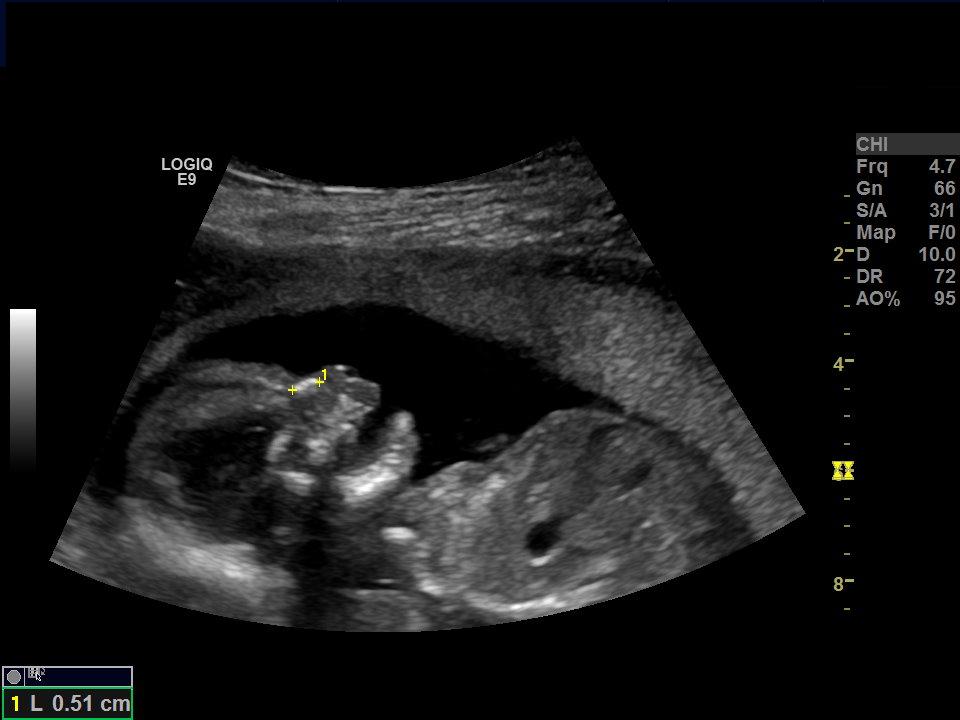

I posted my ultrasound pics from my 12 week 4 day scan previously and I just got back from my 18 week 1 day paid Gender Scan :)

Attachment 39015